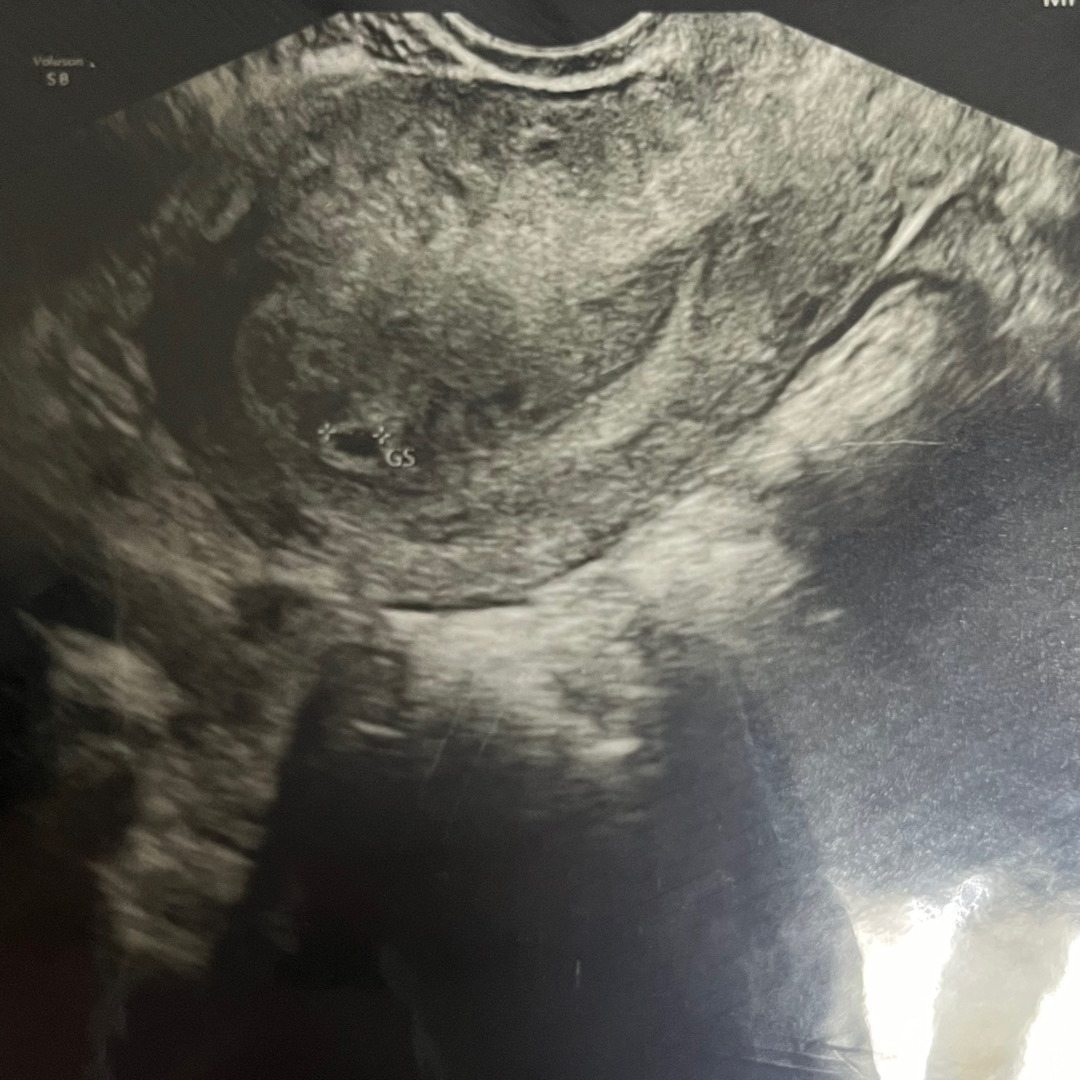

오늘 아기집 보고 왔어용

생시로 하면 4주 4일차에용 ㅎㅎ 선생님은 4주정도로 보이신다는데 ㅎㅎ 오늘 4mm 정도 되는 아기집 보고 왔어용 저는 임테기 역전은 안했는데 너무 궁금해서 원래 오라는 날 보다 더 빨리 갔는데 보고왔어요 ㅎㅎ